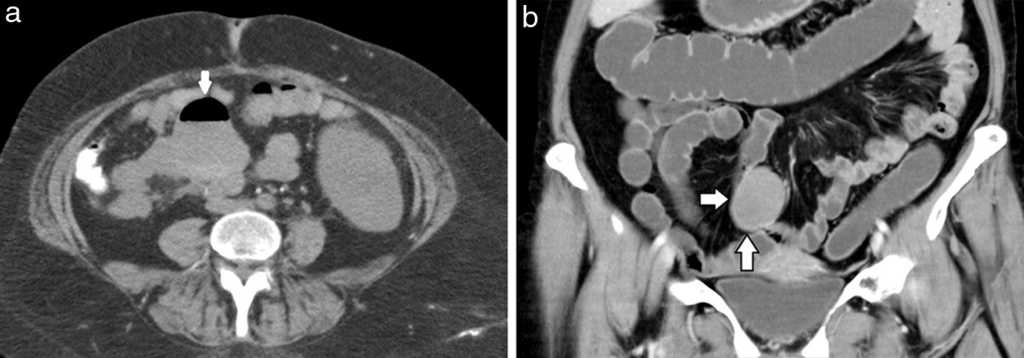

Diverticulitis y perforación (5%): se visualiza engrosamiento parietal y deformación de los contornos del divertículo complicado, con aumento de la densidad de los planos grasos adyacentes y formaciones ganglionares reactivas asociadas, generalmente en rango no adenomegálico. La TCMD descarta o confirma la existencia de colecciones abscedadas o de neumoperitoneo2 (figs. 2–5).

Obstrucción intestinal (3%): se observa obstrucción secundaria al proceso inflamatorio peridiverticular, con un área con cambio de calibre en el punto de partida del divertículo complicado. En el divertículo de Meckel, esta complicación ocurre en el 40% de los casos y se produce por una banda mesodiverticular, un vólvulo del divertículo, un mecanismo de invaginación (fig. 6) o por la extensión a un saco herniario8.